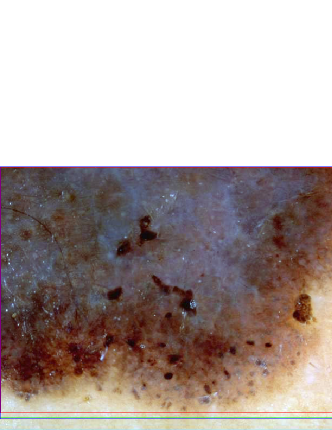

Fig. 5 shows sample bounding box computation results obtained using the ensemble Otsu-Kapur-Huang-Sahoo with P=2𝑃2P=2. It can be seen that the presented method determines an accurate bounding box even for lesions with fuzzy borders. We note that while the expansion operation is useful in most cases, in some cases such as Fig. 5(d), it might deteriorate the results slightly.

Refer to caption

(a) εi=3.26% , εx=1.83%subscript𝜀𝑖percent3.26 , subscript𝜀𝑥percent1.83\varepsilon_{i}=3.26\%\mbox{\; , \;}\varepsilon_{x}=1.83\%

(b) εi=4.89% , εx=3.62%subscript𝜀𝑖percent4.89 , subscript𝜀𝑥percent3.62\varepsilon_{i}=4.89\%\mbox{\; , \;}\varepsilon_{x}=3.62\%

(c) εi=10.87% , εx=4.03%subscript𝜀𝑖percent10.87 , subscript𝜀𝑥percent4.03\varepsilon_{i}=10.87\%\mbox{\; , \;}\varepsilon_{x}=4.03\%

(d) εi=3.18% , εx=4.82%subscript𝜀𝑖percent3.18 , subscript𝜀𝑥percent4.82\varepsilon_{i}=3.18\%\mbox{\; , \;}\varepsilon_{x}=4.82\%

(e) εi=6.75% , εx=5.36%subscript𝜀𝑖percent6.75 , subscript𝜀𝑥percent5.36\varepsilon_{i}=6.75\%\mbox{\; , \;}\varepsilon_{x}=5.36\%

(f) εi=14.24% , εx=9.21%subscript𝜀𝑖percent14.24 , subscript𝜀𝑥percent9.21\varepsilon_{i}=14.24\%\mbox{\; , \;}\varepsilon_{x}=9.21\%

(g) εi=14.05% , εx=10.91%subscript𝜀𝑖percent14.05 , subscript𝜀𝑥percent10.91\varepsilon_{i}=14.05\%\mbox{\; , \;}\varepsilon_{x}=10.91\%

(h) εi=18.36% , εx=13.62%subscript𝜀𝑖percent18.36 , subscript𝜀𝑥percent13.62\varepsilon_{i}=18.36\%\mbox{\; , \;}\varepsilon_{x}=13.62\%

Figure 5: Sample bounding box computation results (εisubscript𝜀𝑖\varepsilon_{i}: initial box error, εxsubscript𝜀𝑥\varepsilon_{x}: expanded box error)